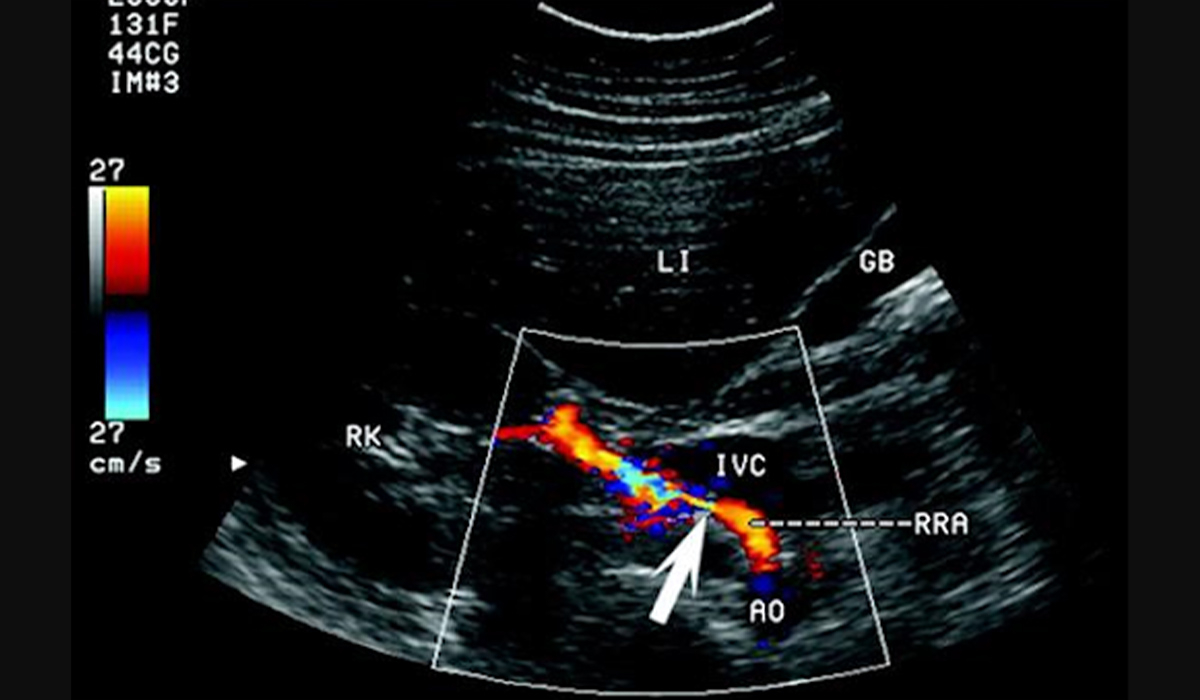

Доплерографія судин шиї показує будову екстракраніальних судин.

УЗД судин головного мозку – інтракраніальних судин.

Спеціаліст УЗД має можливість оцінити будову судин, наявність деформації, патологічних вигинів, об’ємних утворень, показники кровотоку по судинах, чи немає спазмів, проблем з проходженням крові по просвіту судини.

Також є можливість оцінити хребтові артерії, яремні вени шиї, порівнюється симетричність кровотоку з обох сторін.

Під час УЗД судин головного мозку оцінюють передню, середню та задню мозкові артерії та венозні колектори головного мозку і також оцінюють характер кровоплину в судинах.